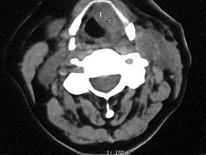

问题 女,54岁,鼻咽部异物感约3个月,PE:左侧声带固定,可见肿物,CT如图所示,应诊断为 ( )

选项 A、慢性增生性喉炎 B、增生型喉结核 C、喉癌 D、喉部血管瘤 E、喉部乳头状瘤

答案 C